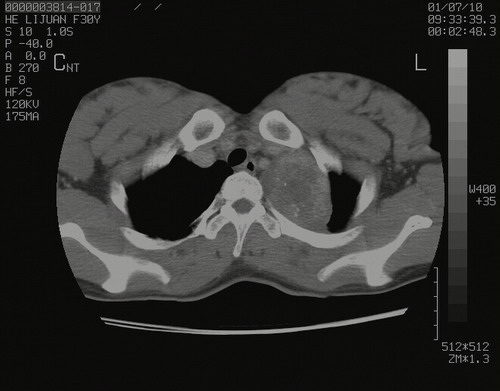

怀孕3个月时(2009-3至4月间),自述突感左侧前后胸疼痛1天,以前胸明显,随后偶感闷痛,余未见异

左肺尖脊柱旁沟肿块,境界清楚,边缘光滑,密度不均,内有多发点片状钙化,考虑良性肿瘤,骨软骨瘤或神经源性肿瘤可能,肺错构瘤不除外。

左后上纵隔见一类圆形肿块影,外侧边界清,密度不均匀,内可见点状钙化影,增强呈不均匀强化,考虑神经源性肿瘤可能。期待病理结果。